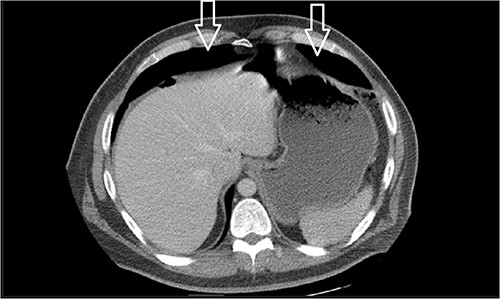

Ten days prior to ER admission, he presented to an outlying hospital with nausea, vomiting and diarrhea episodes and underwent a LC. A baseline computerized tomography scan (CT) demonstrated pneumoperitoneum (see Fig. 1). Because of the lack of inflammatory changes in the GI tract, viscus perforation was an unlikely consideration. An EL was performed that came back negative and he was subsequently discharged.